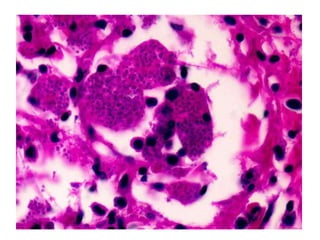

• #48 histoplasma in macrophages

• #49 Slide culture with small microconidia and tuberculate macroconidia Culture shows tan-white-brown wooly mold at 25 - 30 C on Sabouraud dextrose agar Organisms have delicate, septate hyphae, 1 - 2 microns thick, with large rough-walled macroconidia 5 - 15 microns Reverts to yeast at 37 C on sheep blood agar Yeast is 2 - 4 microns, budding, single nuclei, round/oval with thin rigid walls

• #52 Nasal rhinosporidiosis. In the insert, globular cyst containing endospores (Haematoxylin & Eosin, 50×; in the insert, 400× . Each of these cysts represented a thick-walled sporangium containing numerous "daughter spores" in different stages of development (Fig. 1). The stroma contained